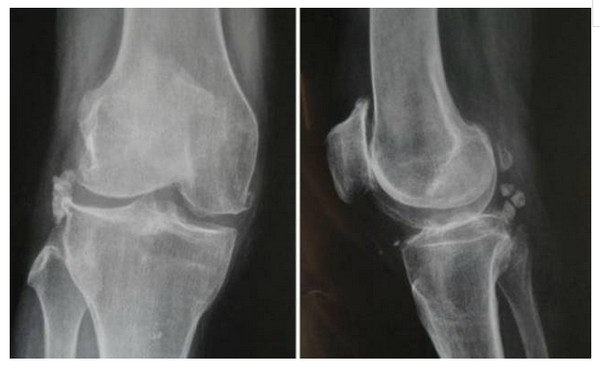

16、骨关节炎

常见(>50岁)

膝关节痛

早期:活动开始时痛、剧院征、上下楼梯时痛、下蹲起立时痛,休息能缓解;

中后期:负重痛、行走痛、夜间痛

短时晨僵 (<20分钟),活动后消失

可有滑膜炎急性发作,关节间隙压痛,活动度减少

关节摩擦音,轻~中度关节积液

X线摄片:负重位前后位、侧位和髌股关节切线位。